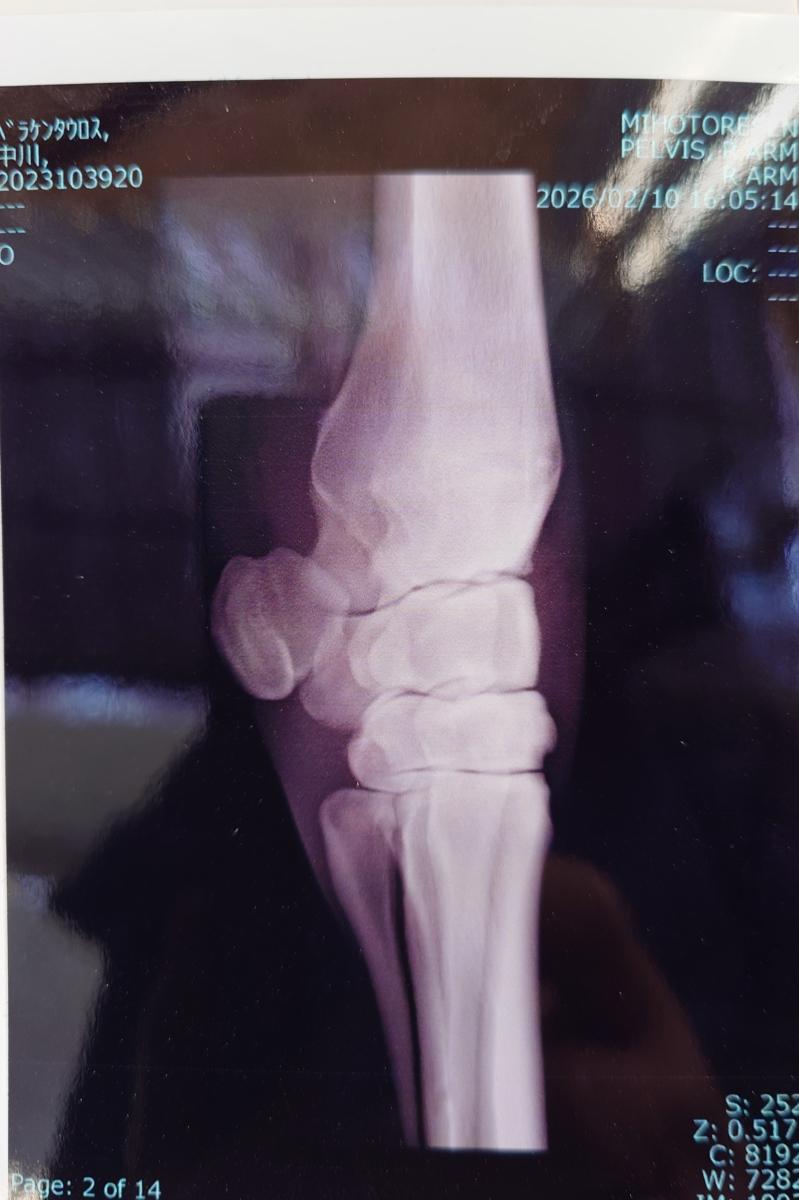

2月7日には京都ダート1400m戦に出走。中団のやや後ろ、12番手のインからレースを進め直線で外に出して追われたものの9着での入線。勝ち馬との着差は1秒4でした。レース後に右前橈骨遠位端骨折が判明。見舞金9号(競走中6カ月)の適用となっています。

なお現状、手術は受けていません。また歩様に出しませんが、触診反応はあります。

※2026年2月7日の競走で、右前橈骨遠位端骨折を発症。事故見舞金9号(競走中の事故により事故発生の日から6カ月以上出走できなくなった場合)を受給しています。